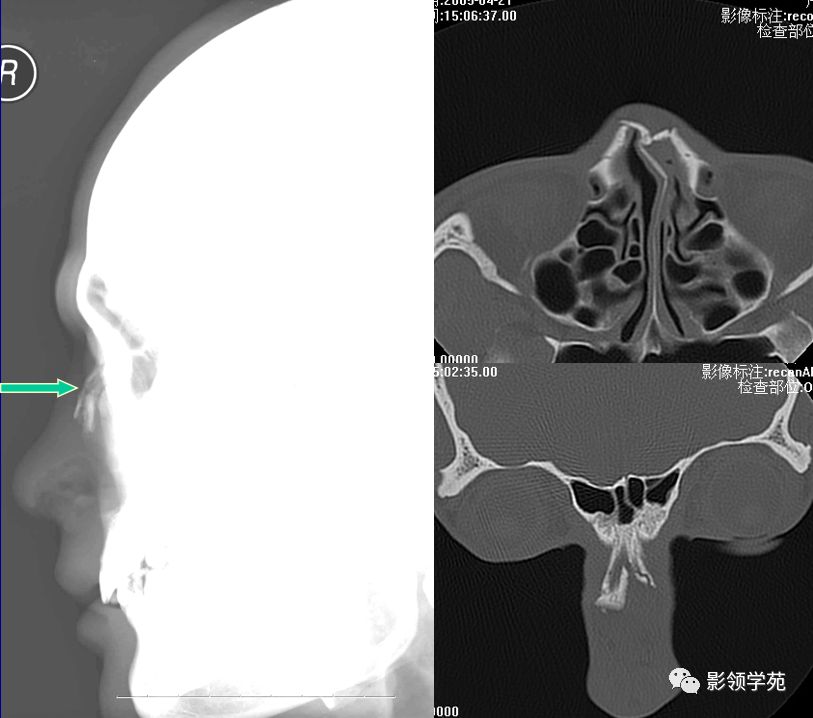

双侧鼻骨骨折

鼻中隔骨折